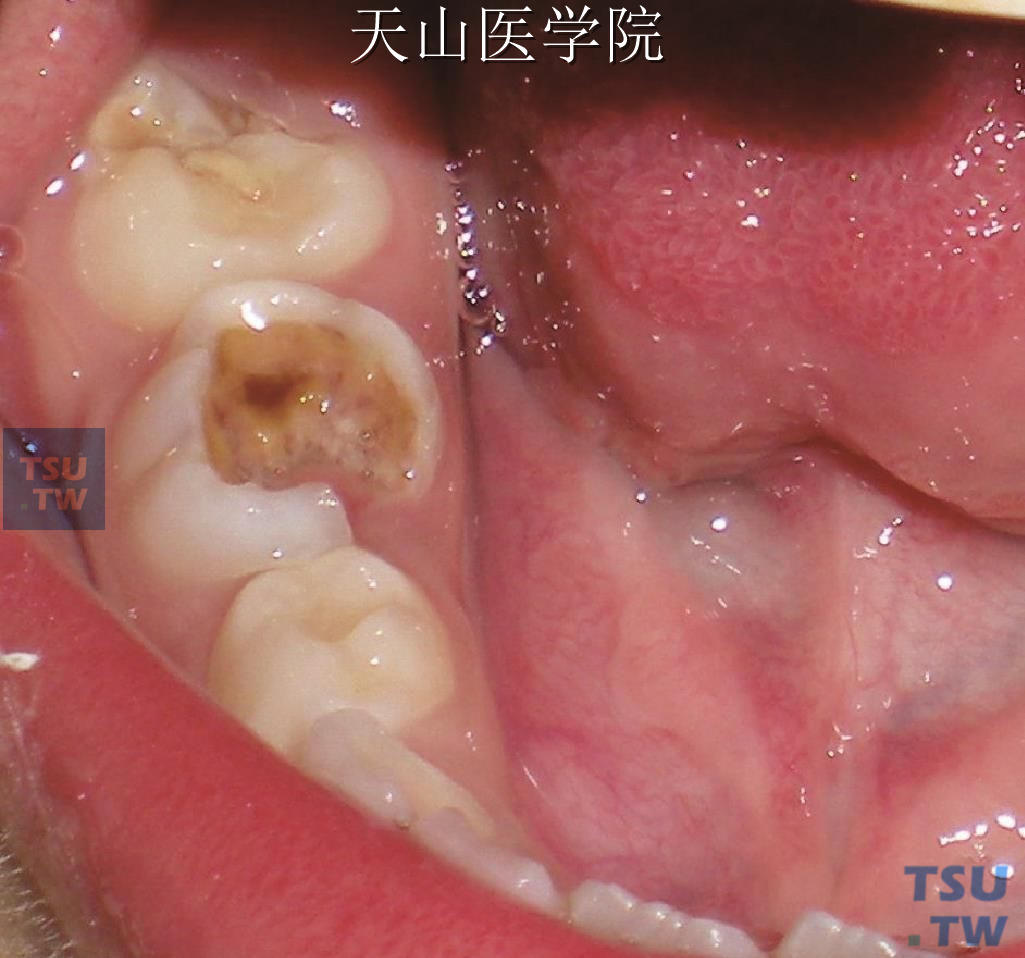

• 儿童龋病

龋病是在细菌为主的多种因素作用下,牙无机物脱矿,有机物分解,导致牙体组织发生慢性进行性破坏的一种疾病,其发病方式以牙体组织崩解为特征,临床表现开始为龋损部位釉质脱矿

根据龋病的临床损害模式,临床上,龋病可以根据破坏进展的速度,龋损发生在牙面的解剖学部位,以及龋损破坏的深度进行分类。按龋损破坏的进展速度分类一、急性龋:急性龋(acute c

• 龋病(蛀牙)的症状表现

龋病的破坏过程是牙体组织内脱矿与再矿化交替进行的过程,当脱矿速度大于再矿化,龋病发生。随着牙体组织的无机成分溶解脱矿,有机组织崩解,病损扩大,从釉质进展到牙本质。在